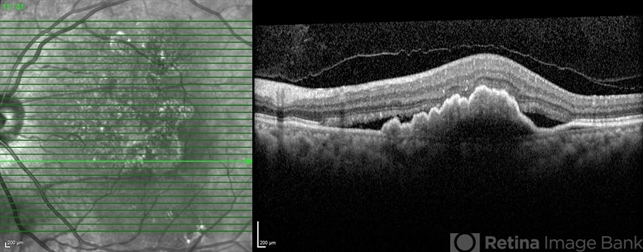

- Polypoidal choroidal vasculopathy

- polypoidal choroidal vasculopathy (PCV)

- SD- OCT of the left eye of a 65 year old man revealing multilobulated large PED.